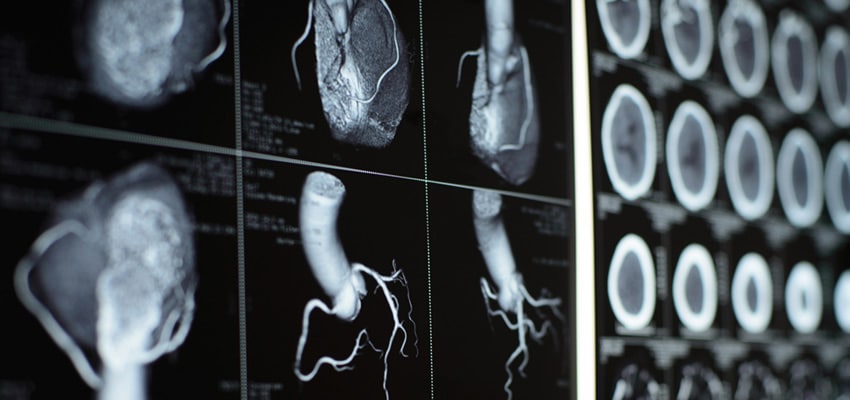

انجام اسکن هسته ای قلب به روش اسپکت تهران : اسکن پرفیوژن میوکارد با SPECT (Single-Photon Emission Computed Tomography) تصویربرداری هستهای است که جریان خون (پرفیوژن) ماهیچهٔ قلب را در حالت استرس و در حالت استراحت نشان میدهد. این روش بهطور معمول برای تشخیص ایسکمی (کاهش جریان خون ناشی از تنگی عروق کرونری)، تعیین وسعت